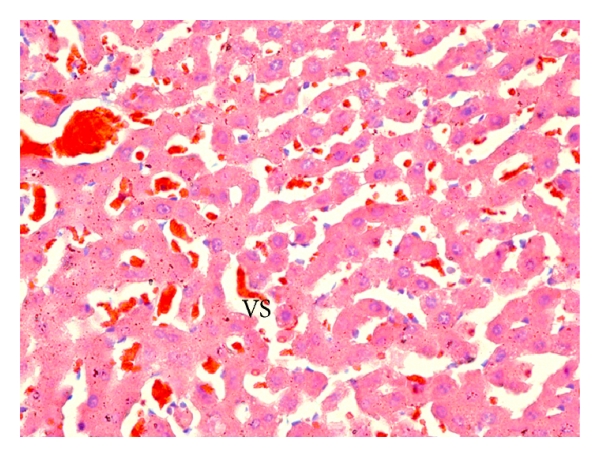

Microscopic observations revealed normal histology with regular morphology of the liver tissue in the control (Figure 8(a)) and B. trimera groups (Figure 8(b)). In the APAP-intoxicated group (Figure 8(c)), cellular damage was visible in the form of hydropic degeneration, inflammation, and hemorrhage. The B. trimera treatment (Figure 8(d)) considerably improved the liver morphology in comparison to the APAP-intoxicated rats.

To confirm the hepatoprotective effect of B. trimera extract against the damages caused by APAP, histopathological analyses were performed. APAP-intoxicated animals treated with the B. trimera extract had improved histopathology compared to the APAP-intoxicated group without treatment.